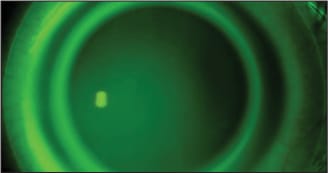

For a spherical cornea, fitting the lens 0.50D steeper than the keratometric curve provides enough clearance for tears to reside under the central portion of the lens (Figure 5). For example, for a spherical eye with K readings of 43.00 / 43.00 we will select a lens 0.50D steeper (43.50D or 7.76mm), which results in a SynergEyes base curve of 7.70mm. Application of this base curve selection method (selecting a base curve 0.50D steeper than the flat K) is indicated for corneas that are spherical or mildly toric (up to 0.87D of toricity).

Figure 5. Properly fit SynergEyes lens. Notice the flow of tears.